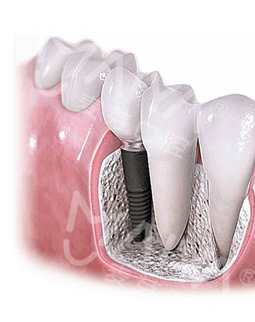

除此之外,我还和在场的观众,共同见证了种植体坚固力。都说种植体可以在口内待一辈子甚至更久,这次我倒真的见识了,为什么一颗小小的牙钉真的可以媲美真牙了!4颗牙钉吊起了一个成年人的重量,经受住两个成年人踩压的重量,相信以后我再也不用单侧咀嚼了!

经过医护人员的严密术前检查和准备工作后,顺利进入了三通道无菌手术室,接受种植博士专家团此前为其量齿定制的全数字化精确种植牙手术,一颗牙种出来真的只需要5分钟,我还没有任何感觉,医生说已经种好了,不得不感叹科技技术发展快、医生技术高超,而且第一次种牙就赶上了“工程”行动,非常幸运,对我们普通百姓来说"工程"援助非常实在,希望"工程"启动能帮助更多的人,毕竟缺牙人很多,祝愿大家都能像我一样在麦芽口腔种好牙,享口福。"